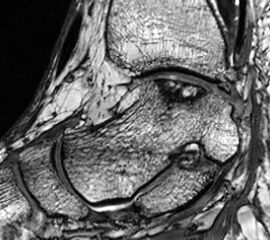

Magnetresonanztomographie (MRT)

Im Laufe der Jahre hat sich die Magnetresonanztomographie (MRT) als sehr gute Option zur bildgebenden Diagnostik erwiesen. Die besonderen Vorteile liegen in der guten Beurteilbarkeit der Weichteilstrukturen und der Nichtinvasivität ohne Notwendigkeit der Verwendung von Röntgenstrahlen. Prinzipiell können alle geforderten Eigenschaften der Pathologie incl. der Veränderungen des subchondralen Knochens und des darüberliegenden Knorpels sowie der gelenkumgebenden Weichteilstrukturen visualisiert werden. Daher wird die MRT als Wichtigste anzufertigende Bildgebung angesehen 1720.

Die technischen Kenndaten der optimalen MR-Diagnostik von osteochondralen und chondralen Läsionen am Talus sind komplex und werden in der Literatur heterogen dargestellt. Grundsätzlich wird empfohlen ein Gerät mit einer Feldstärke von 0.5 – 3 Tesla zur Verfügung zu haben 17. In eigener Erfahrung lässt sich allerdings auch schon mit Niederfeldgeräten von 0,2 Tesla eine gute Beurteilbarkeit der Läsionen erreichen 21

Die Standardsequenzen umfassen Fast-Spin-Echo (FSE) und Gradientenechosequenzen 22. Die Pulssequenzen umfassen typischerweise Protonendichte (PD) und fettunterdrückte Protonendichte Sequenzen (PD-FS) 17. In unserem eigenen Protokoll verwenden wir aktuell isotrope 3D-Gradientenechosequenzen (true FISP) (Abb. 3), protonendichte-fettunterdrückten Turbo-Spin-Echo-Sequenzen (PD-FS-TSE) (Abb. 4 und 5) und T1-gewichtete Spinechosequenzen (Abb. 6). Wichtig ist letztendlich die räumliche Auflösung als Funktion der Schichtdicke, dem Blickfeld (FOV) und der Bildmatrix 17.